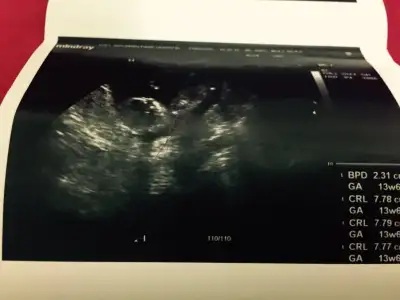

Kizlar bnm bebisimede bakarmisinz rica etsem,doktor 16.haftayibekle dedi,biz 13. Haftadayiz..

o gördüğümüz nub ise açılı sanırım erkekKizlar bnm bebisimede bakarmisinz rica etsem,doktor 16.haftayibekle dedi,biz 13. Haftadayiz..